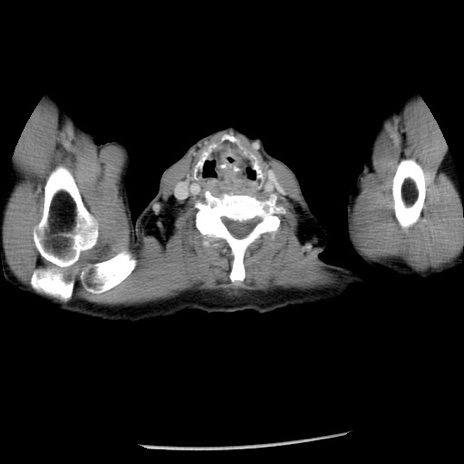

症例26(横断像)

【症例】80歳代男性

【主訴】嘔吐

【現病歴】昨晩2回嘔吐あり、今朝になっても嘔吐あり。来院。

【既往歴】胃潰瘍

【身体所見】意識清明、BT 37.6℃、BP 166/95mmHg、HR 100bpm、SpO2 97%、腹部:平坦・軟、腸蠕動音聴取良好、圧痛なし。

【データ】WBC 21900、CRP 1.46